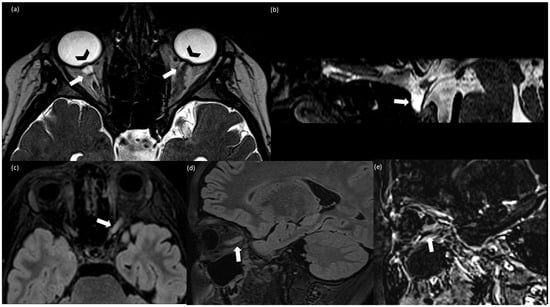

| 5/ Alqahtani et al., 2023 [7] | 12/M | 28.8 | 35 | Normal | 75 (89% L, 4% N, 3% M, 1% E) | No | flattening of the posterior globes, prominent both Meckel cave, optic nerves tortuosity | Headache Bilateral reduced visual acuity | asymmetric bilateral papilledema and abnormal visual acuity and visual field. | Acetazolamide, methylprednisolone 30 mg/kg/day was administered for 5 days followed by low doses acetazolamide 10 mg/kg/day (duration treatment 3 months) |

| 6/ Valdrighi et al., 2021 [8] | 12/M | BMI not specified Obese | 52 | Normal | 157 (68% L, 11% N, 17% M, 4% E) | No | a partially empty sella, intraocular protrusion of the optic nerves, flattening of the posterior globes, narrowing of the venous sinuses, and tortuous optic nerves multifocal leptomeningeal enhancement. After 4 months from the onset: T2 hyperintense cerebellar and pontis lesions | Blurred vision, nausea, vomiting, headaches, cranial nerve VI palsies. | Bilateral papilledema Normal visual acuity and visual field. | Acetazolamide, methylprednisolone. After radiological relapse: monthly IV immunoglobulin |